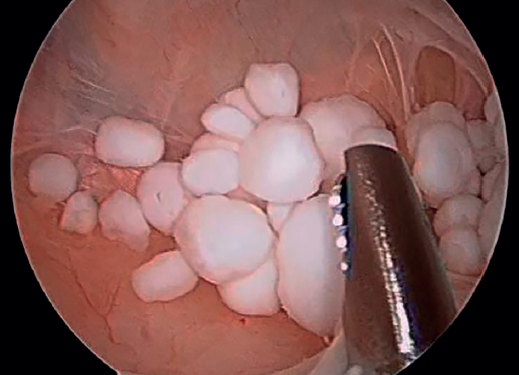

Inicialmente, se realizó una artroscopia diagnóstica a través de los portales anterolateral y anteromedial estándares, en la que se identificó una rotura degenerativa del menisco medial, que se regularizó con instrumental motorizado y vaporizador de radiofrecuencia. A continuación, se realizó un portal posteromedial bajo visión directa intraarticular, para explorar el compartimento posterior de la rodilla. Durante la exploración, se localizó el orificio de entrada del quiste poplíteo, cerrado por una capa de tejido sinovial, que fue desbridado con instrumental motorizado a través del portal posteromedial. Esto permitió acceder al interior del quiste de Baker, donde se hallaron múltiples cuerpos libres de aspecto y consistencia cartilaginosa (Figura 2). Dada la dificultad de acceso a dichos cuerpos libres, se decidió la realización de un portal transgastrocnemio (Figura 3): bajo visión directa, con la óptica en el portal posteromedial habitual, se marcó el punto de entrada al quiste con una aguja Abbocath® a través del gastrocnemio medial. El portal se situó en la región proximal del gastrocnemio, a la altura aproximada de la localización del quiste –determinada por la combinación de palpación y visualización directa con el artroscopio–, desde el lado medial para evitar las estructuras neurovasculares poplíteas. Una vez colocado el Abbocath® como guía en la posición deseada, se procedió a la realización del portal mediante una incisión longitudinal de 0,5 cm con bisturí del n.º 11. Este abordaje facilitó el acceso al interior del quiste, pudiéndose realizar la exéresis de los cuerpos libres previamente identificados de forma extraarticular directa, evitando así la diseminación dentro de la articulación (Figura 4). Finalmente, se realizó un desbridamiento de las paredes del quiste a través del mismo portal transgastrocnemio (Figura 5). El material resecado se envió para su estudio anatomopatológico.